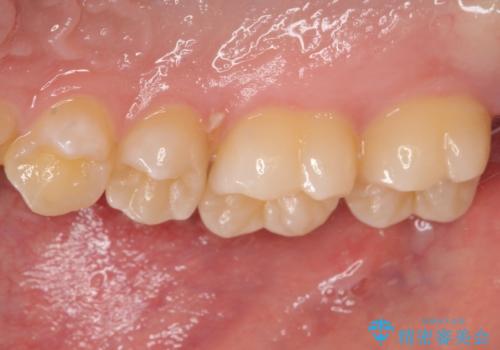

歯間部の自分では気づきにくい虫歯 セラミックインレー修復

- 定期健診で歯間部の齲蝕が見つかった患者様です。

食べ物が頻繁に詰まるとのことで、レントゲンで確認したところ、歯間部に齲蝕が認められました。

このまま放置すると齲蝕が進行し、歯の神経まで及んでしまう危険性があるため、精度の高いセラミックインレー修復を行いました。

ぱっと見ではわかりずらい齲蝕ですが、レントゲン写真でははっきりと確認することができます。